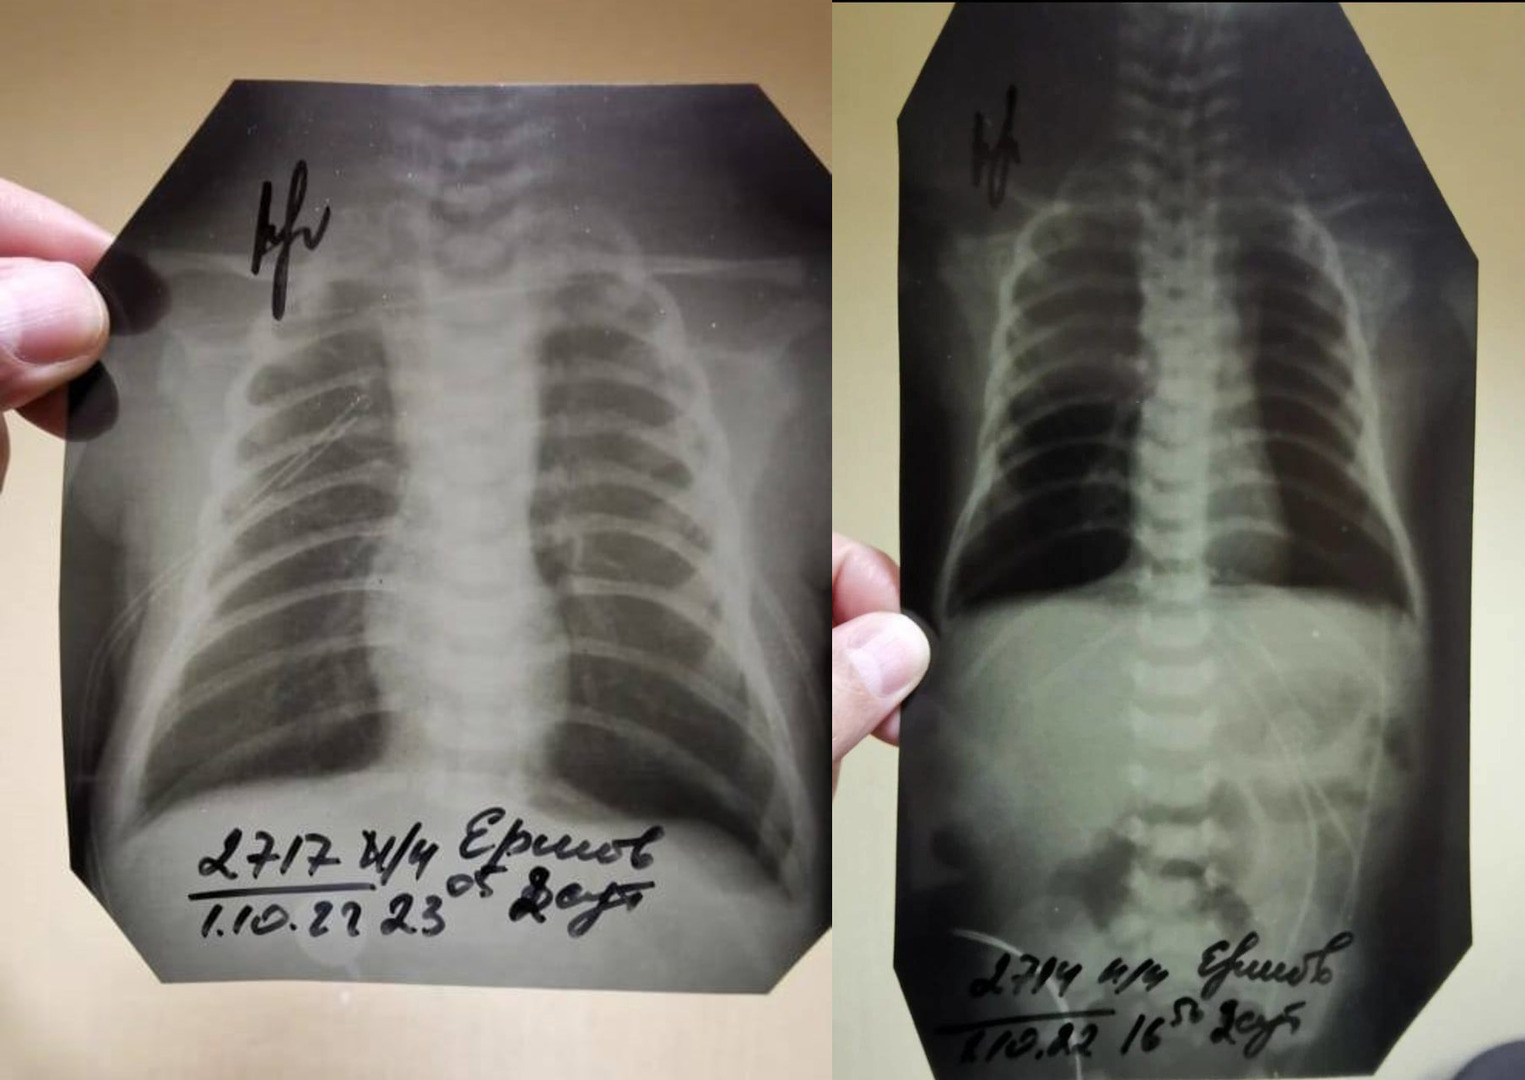

Интересно и то, что отцу препятствуют в ознакомлении материалов дела, заявляет сам Ершов. Странности в уликах тоже есть — например, если в прошлом году следователи говорили, что рентгеновские снимки были утеряны больницей, то после жалоб их вдруг нашли, как утверждает отец. Только есть одна деталь — место, в котором обычно аппарат печатает ФИО пациента, врача, проводившего рентген, дату и время процедуры, было вырезано на всех снимках. («Страсти» ознакомились с результатами рентгена).

«Все эти данные обрезаны. Видно, что обрезали это ножницами или чем-то ещё, криво, косо. И просто обычным маркером подписано: Ершов В. Д. Мой сын. А вместо ФИО врача, который проводил процедуру, просто стоит подпись. Интересно, что каждый снимок делался в разные дни и в разное время, а подписи стоят на всех 21 снимках одного и того же врача. Он что, один работает без выходных?», — добавил он.

Обрезанные флюорографические снимки ребенка

Обрезанные флюорографические снимки ребенкаПредоставлено героем публикации

Сам Ершов считает, что снимки, которые внезапно нашлись, на самом деле не принадлежат его ребенку.

Рассказывая об обрезанных снимках, Кириленков допустил, что такое возможно при использовании старого оборудования.

«Да, такое допускается, когда рентген делают на старом оборудовании — по старинке пишут ручкой либо маркером», — добавил он.